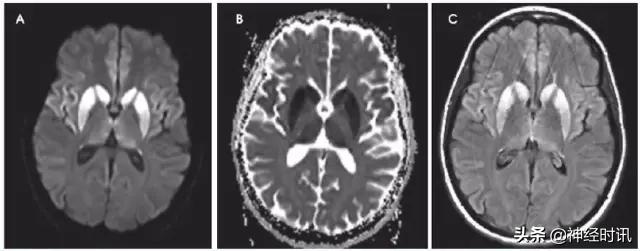

一氧化碳中毒

轻型患者常出现双侧苍白球对称性弥散受限和T2高信号(图12)。严重病例中基底节其余部分、丘脑、海马、幕上白质、胼胝体以及少数情况下大脑皮质均可受累。随后临床症状一过性改善,可能发生迟发型脑病,表现为双侧融合性脑室旁白质T2高信号和片状弥散受限。急性期的弥散受限可能继发于细胞毒性水肿,迟发期可能与脱髓鞘有关。

图12 一例49岁男性,在炭火旁野营后次日晨起被人发现存在凝视、口吐泡沫,意识尚清,呼吸6次/分,碳氧血红蛋白水平22.9。MRI显示双侧苍白球弥散受限(A:DWI,B:ADC)和T2-FLAIR高信号(C:T2WI,D:FLAIR)。